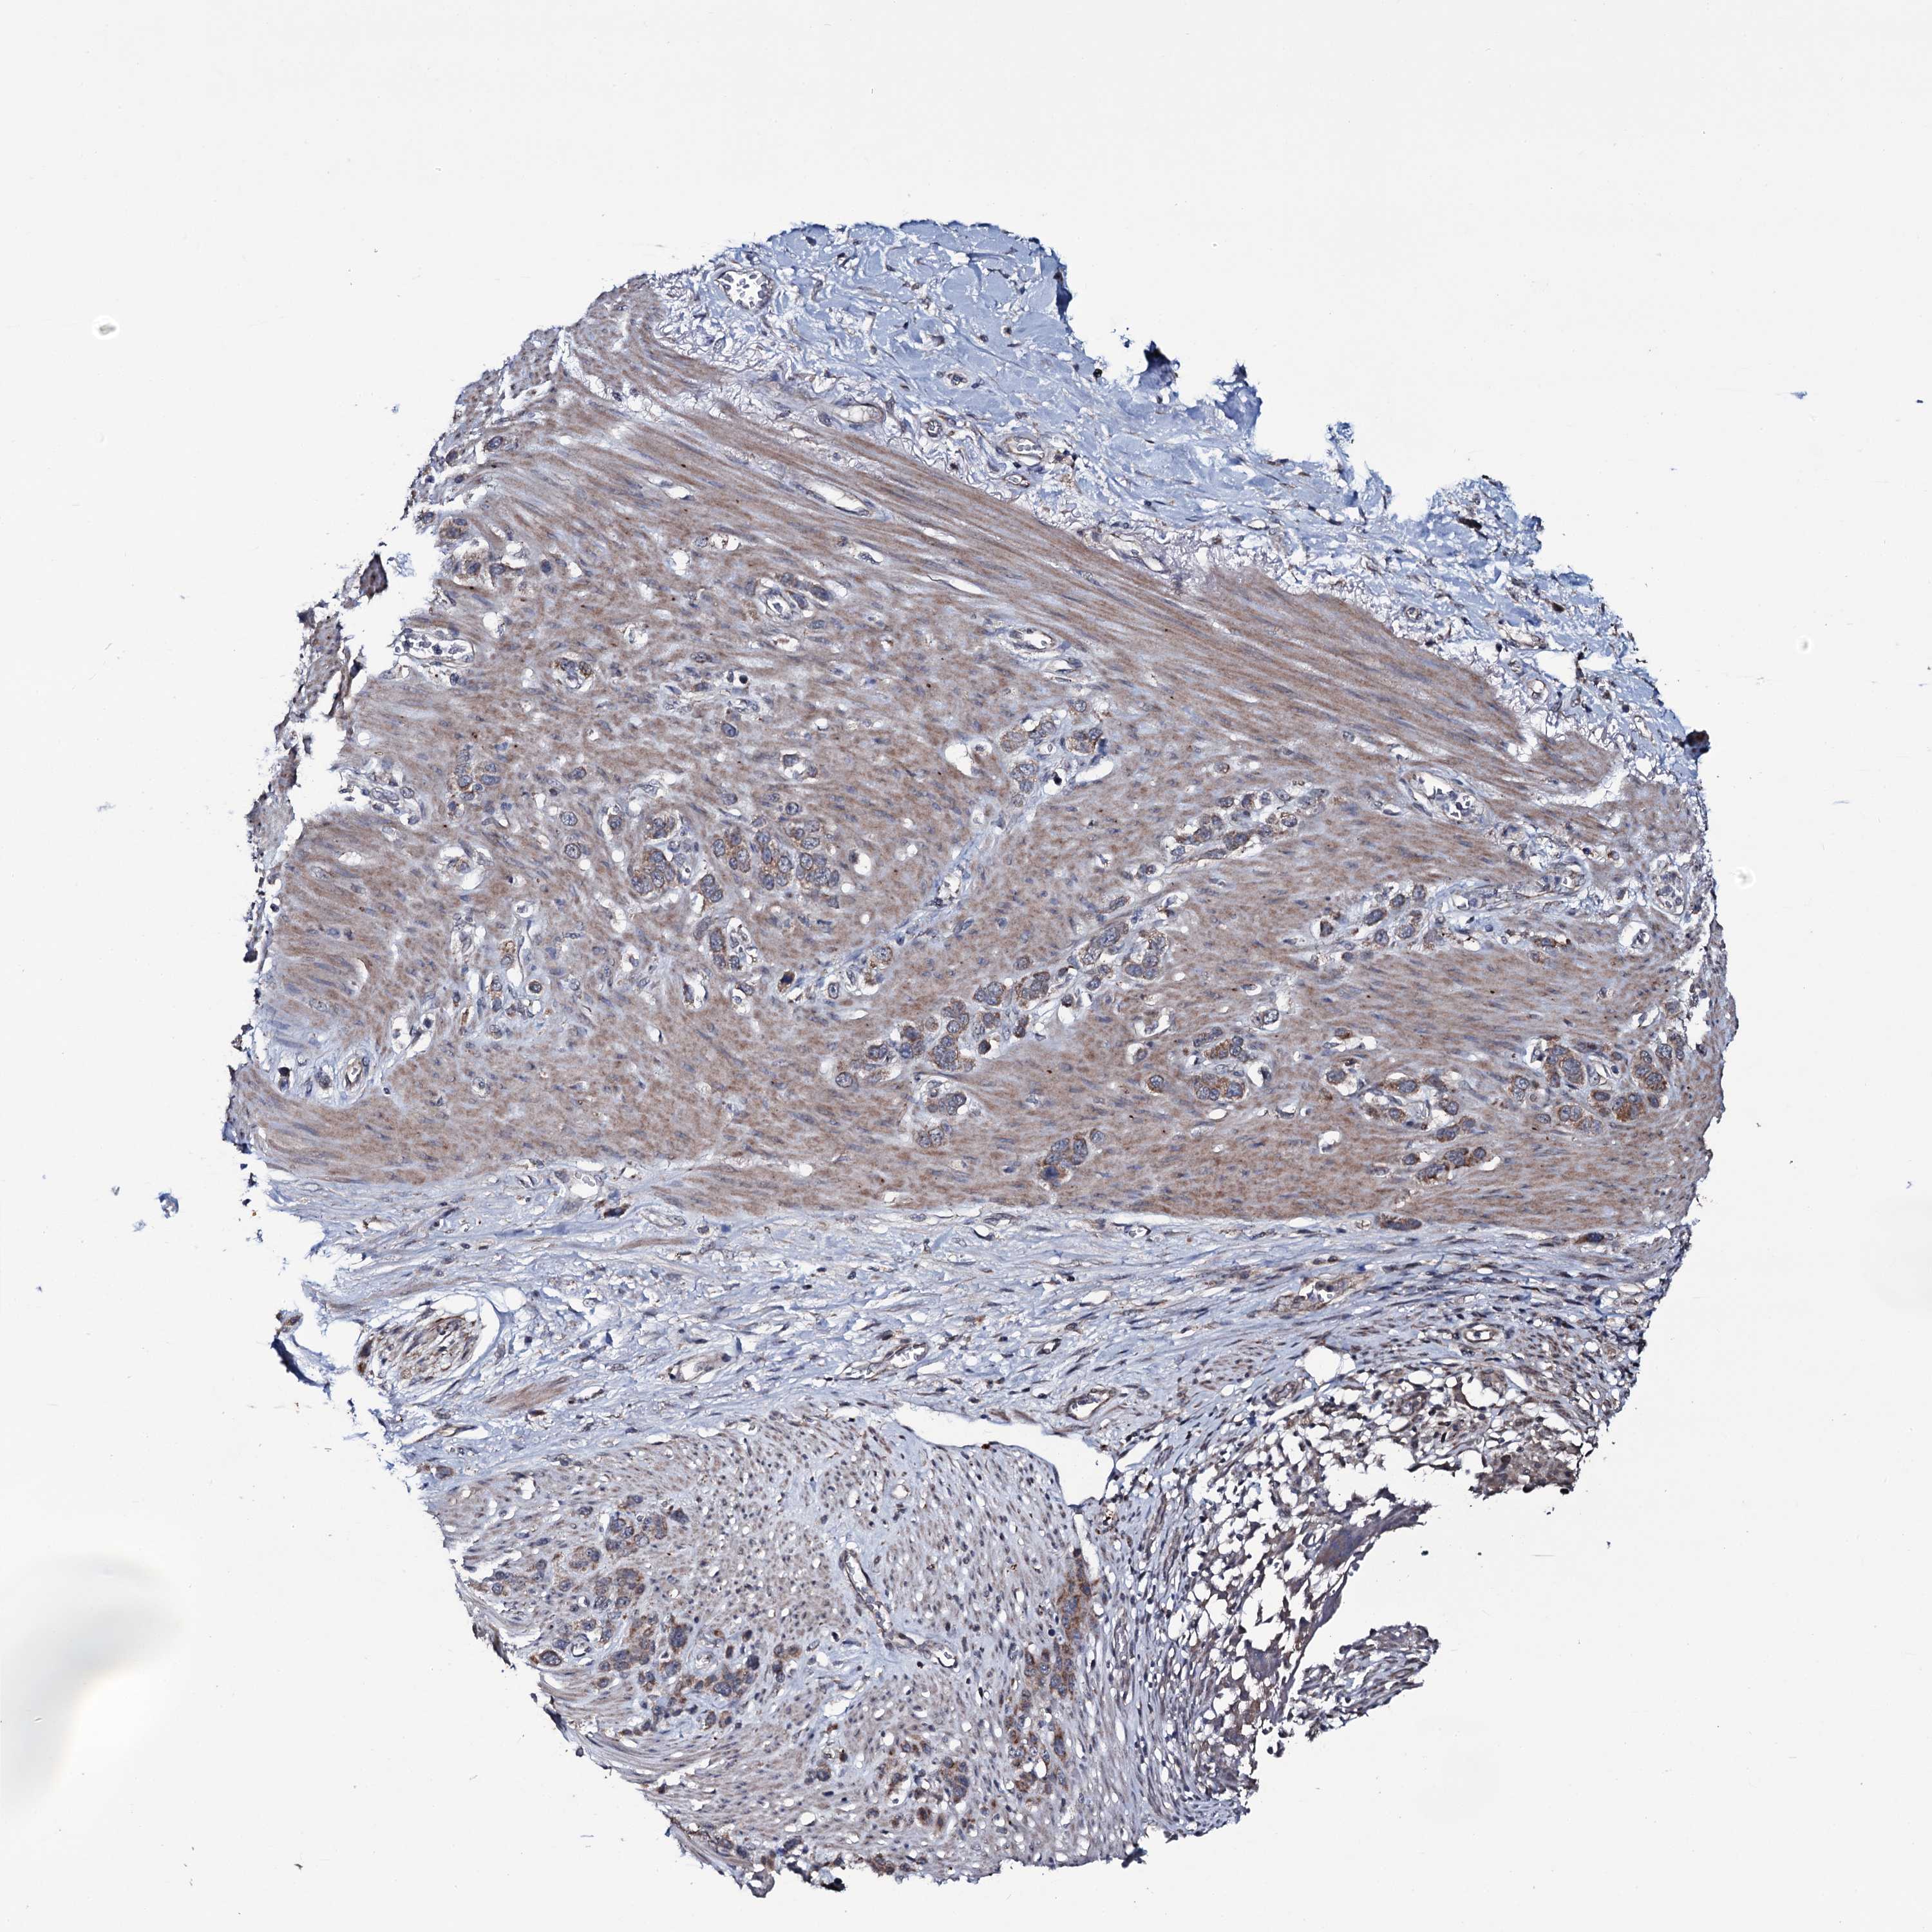

STOMACH CANCER - Protein expressioni

A mouse-over function shows sample information and annotation data. Click on an image to view it in a full screen mode. Samples can be filtered based on level of antibody staining by selecting one or several of the following categories: high, medium, low and not detected. The assay and annotation is described here.

Note that samples used for immunohistochemistry by the Human Protein Atlas do not correspond to samples in the TCGA dataset.

Antibody stainingi

Antibody staining in the annotated cell types in the current human tissue is reported as not detected, low, medium, or high, based on conventional immunohistochemistry profiling in selected tissues. This score is based on the combination of the staining intensity and fraction of stained cells.

Each image is clickable and will lead to virtual microscopy that enables deeper exploration of all samples and also displays staining intensity scores, fraction scores and subcellular localization as well as patient and tissue information for each sample.

Antibody HPA039083

Antibody HPA046344

Staining

High

Medium

Low

Not detected

Intensity

Strong

Moderate

Weak

Negative

Quantity

>75%

75%-25%

<25%

None

Location

Nuclear

Cytoplasmic/membranous

Cytoplasmic/membranous,nuclear

Adenocarcinoma, NOS

Adenocarcinoma, High grade